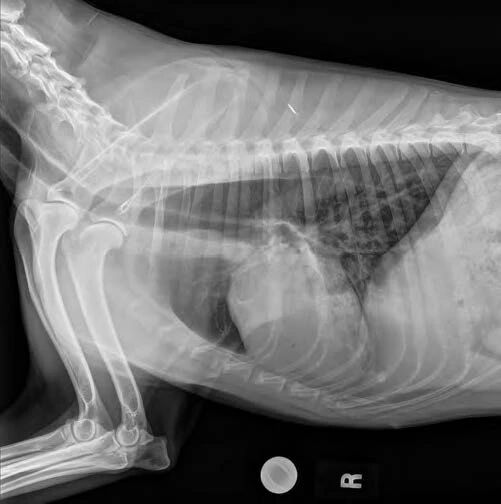

- 胸部X光片:食管弥漫性扩张。

- 食管可以充满空气、液体或食物。

–如果存在吸入性肺炎,可见肺浸润(图1-2)。

图1. 侧面胸部X光显示食管扩张和吸入性肺炎。